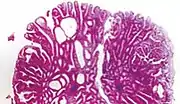

| Type | Risk of containing malignant cells | Histopathology | Image | |

| Hyperplastic polyp | 0% | No dysplasia.[10]

|

![]() | |

Hyperplastic polyp

Most hyperplastic polyps are found in the distal colon and rectum.[18] They have no malignant potential,[18] which means that they are no more likely than normal tissue to eventually become a cancer.